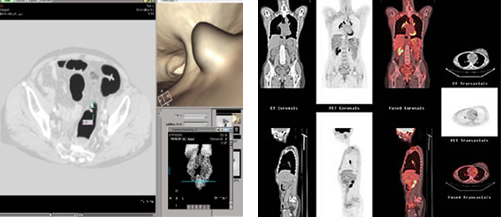

• 복부 CT, MRI

• 전산화 단층촬영(CT)

주로 대장암을 진단하고 암이 주변 장기나 간, 림프절 등으로 전이 되었는지 알아보는데 가장 널리 사용되는 검사이다. 검사 전날 특별한 처치는 필요하지 않으며 검사 당일 8시간 정도의 금식이 필요하고 정확한 검사를 위해 정맥주사를 통해서 조영제를 주입 받고 검사를 받는다. 이때 신장의 기능이 떨어져 있는 환자나 조영제에 알레르기 반응, 즉 조영제 주사 후 심한 구토, 피부 발적, 두드러기, 가려움증, 목이 붓고 쉬는 듯한 증상을 보인 적이 있는 환자는 검사 전에 담당의사와 상의해야 한다.

• 자기공명영상(MRI)

CT검사에서 간 전이가 명확하지 않거나 간으로 전이된 암의 개수를 정확히 파악하고자 할 때 보조적으로 사용된다. 직장암의 경우 직장 주변으로 암이 얼마나 퍼졌는지 알아보는데 유용하여 직장암 진단 후 치료 방침 결정하는데 도움이 된다. CT검사와 다른 종류의 조영제 주사를 이용하므로 CT검사에서 사용되는 조영제에 부작용을 반응을 보이는 경우에도 검사 할 수 있다. 그러나 검사비가 비싸고, 검사 시간도 CT검사에 비해 길며, 좁은 원통형 공간에 들어가 검사를 하므로 폐쇄

• 양전자방출 단층촬영(PET) 및 PET-CT 검사

일반적으로 암세포가 정상세포에 비해 대사활동이 빠른 점을 이용하여 포도당에 양전자 방출체를 표지물질로 부착시켜 주사한 후 표지물질로부터 방출되는 감마선으로 암세포를 발견하는 검사법이다. 그러나 이 검사로부터 얻어지는 영상은 암의 정확한 위치가 어디인지 구별하기 어려울 때도 있고 암이 아닌 염증성 변화에도 양성을 보이는 단점이 있다. 이러한 단점을 보완하기 위해 PET검사와 함께 CT검사도 시행하여 두 검사의 결과를 하나의 영상으로 조합하는 PET-CT검사가 새로이 개발되었다. 이 검사는 단독으로 시행되는 일은 드물며 수술 전 CT에서 간 전이 등이 의심될 때 MRI검사와 함께 간 내의 전이암 개수의 정확한 파악이나 타 장기로의 전이를 확인하고자 할 때 사용되기도 하고 특히 수술 후 추적 CT검사에서 재발 또는 전이가 의심되는 경우에 추가로 사용된다.